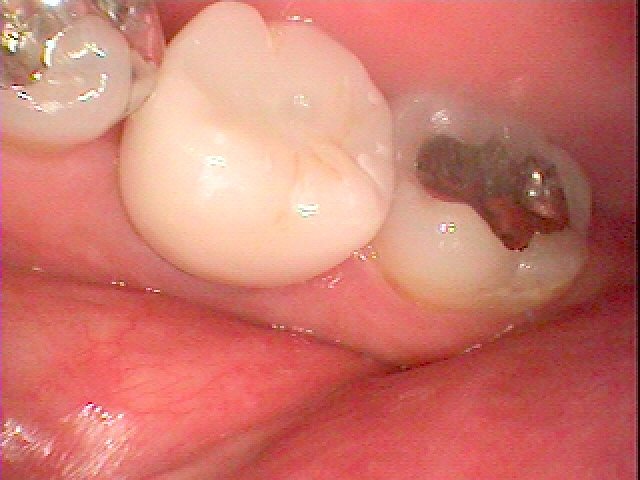

1年後になります

変わらずの色調、マージンの位置を保っています